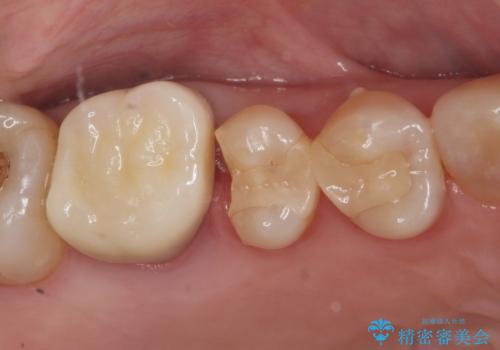

e-maxインレーによる治療

- 定期検診で来院してレントゲンを撮ったところ

歯と歯の間にう蝕ができていました。

拡大鏡下でう蝕を全て除去してe-maxインレーにて治療を行いました。

- e-maxインレー 7.7万円 費用は治療当時の料金となります

e-maxインレーは二次的にう蝕になるリスクが

銀の詰め物や樹脂の詰め物に比べて低いです。